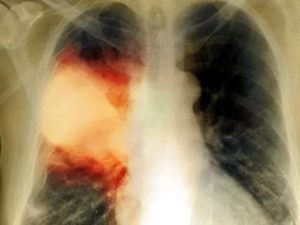

Как узнать, что пневмония вылечена, когда присутствует кашель? Требуется выполнить рентген легких. Иногда наблюдаются остаточные явления после пневмонии на рентгене – небольшие затемнения на лёгочной ткани хорошо видны на плёнке. После перенесённого воспаления лёгких на лёгочной ткани наблюдаются:

Самым распространенным методом диагностики легких является – флюорография. Но если врач подозревает, что у пациента есть спайки, то больной отправляется на рентген. По рентгеновскому снимку распознать синехию можно по мутным темным пятнам. Она выглядит, как теневое затемнение и неподвижна при вдохе и выдохе.

Плевродиафрагмальная спайка на снимке рентгена

Иногда выявляется деформация грудной клетки и диафрагмы. Чаще всего спаечный процесс отмечается в нижней части легкого. Такой вид спаек – плевродиафрагмальный, а вид спаек в верхней части – плевроапикальный.